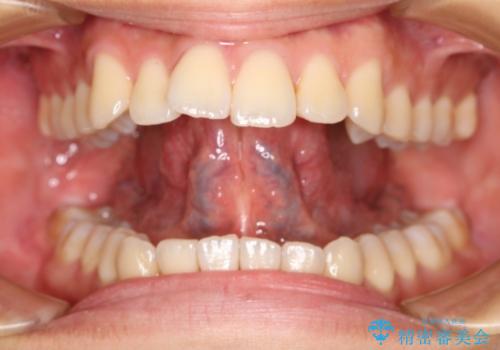

今回のケースではレーザー機器を用いて手術を行いました。これにより従来のメスを使用する術式と比べて所要時間の短縮が図れ、かつ縫合を必要としないため術後の不快感も軽減することができます。

舌小帯切除術を行った際、そのままただ経過を診ているだけだと切除した靭帯がまた短い状態で治癒してしまうことが予測されます。また、今まで限られた範囲内のみで運動していた舌は通常の環境下の舌と比較して筋力か弱い傾向にあります。

このような場合せっかく手術を行っても効果が減弱してしまうので、手術効果を最大限に高めるために当院では「MFT(筋機能訓練)」を併用することをお勧めしています。

筋機能訓練とは舌が本来取るべき自然なポジショニングへの誘導や、使っていなかった筋肉を動かすことで舌の筋肉量の底上げを行うことを目的とした舌運動トレーニングです。